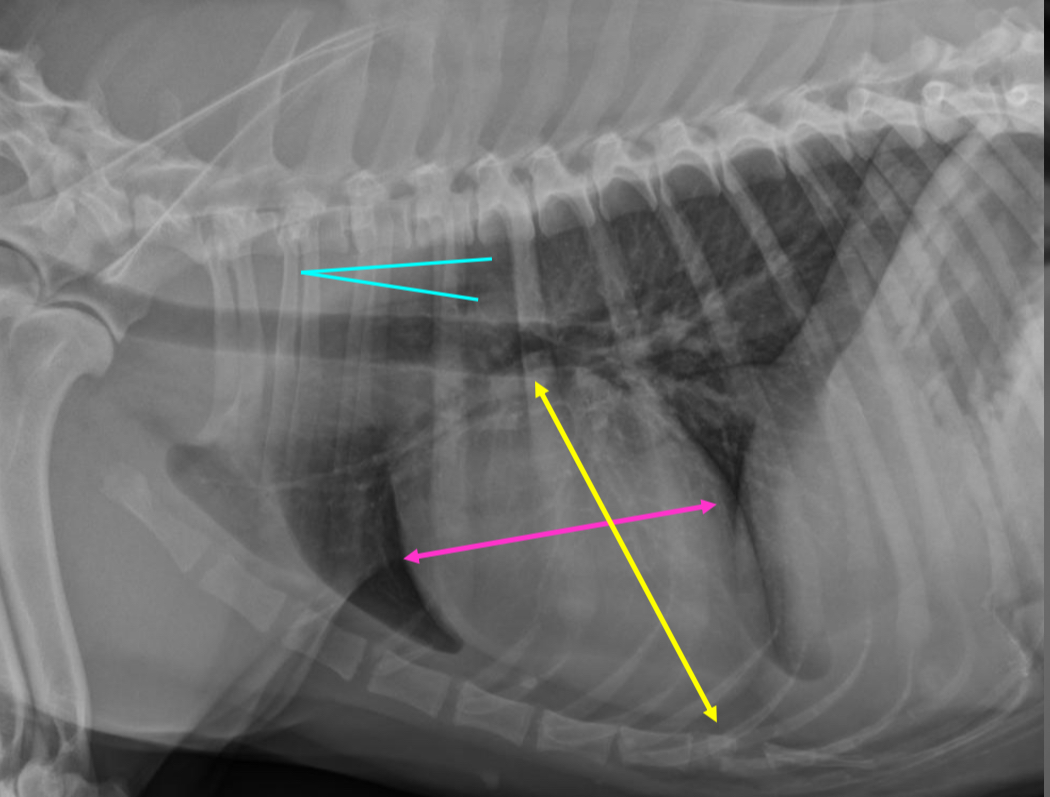

2 features of RVE on lateral

-wide cardiac silhouette

-cr.margin super bowed out —> increased sternal contact

What part of heart is enlarged?

RVE

2 features of RVE on VD

-bulge 5-9 o’clock

-reverse D

What part of the heart is enlarged

2 features of RAE on lateral

-dorsal bowing of trachea over cranial heart base @ bifurcation

-loss of cr.cardiac waist (R.atrium and MPA are here)

What part of the heart is enlarged?

RAE